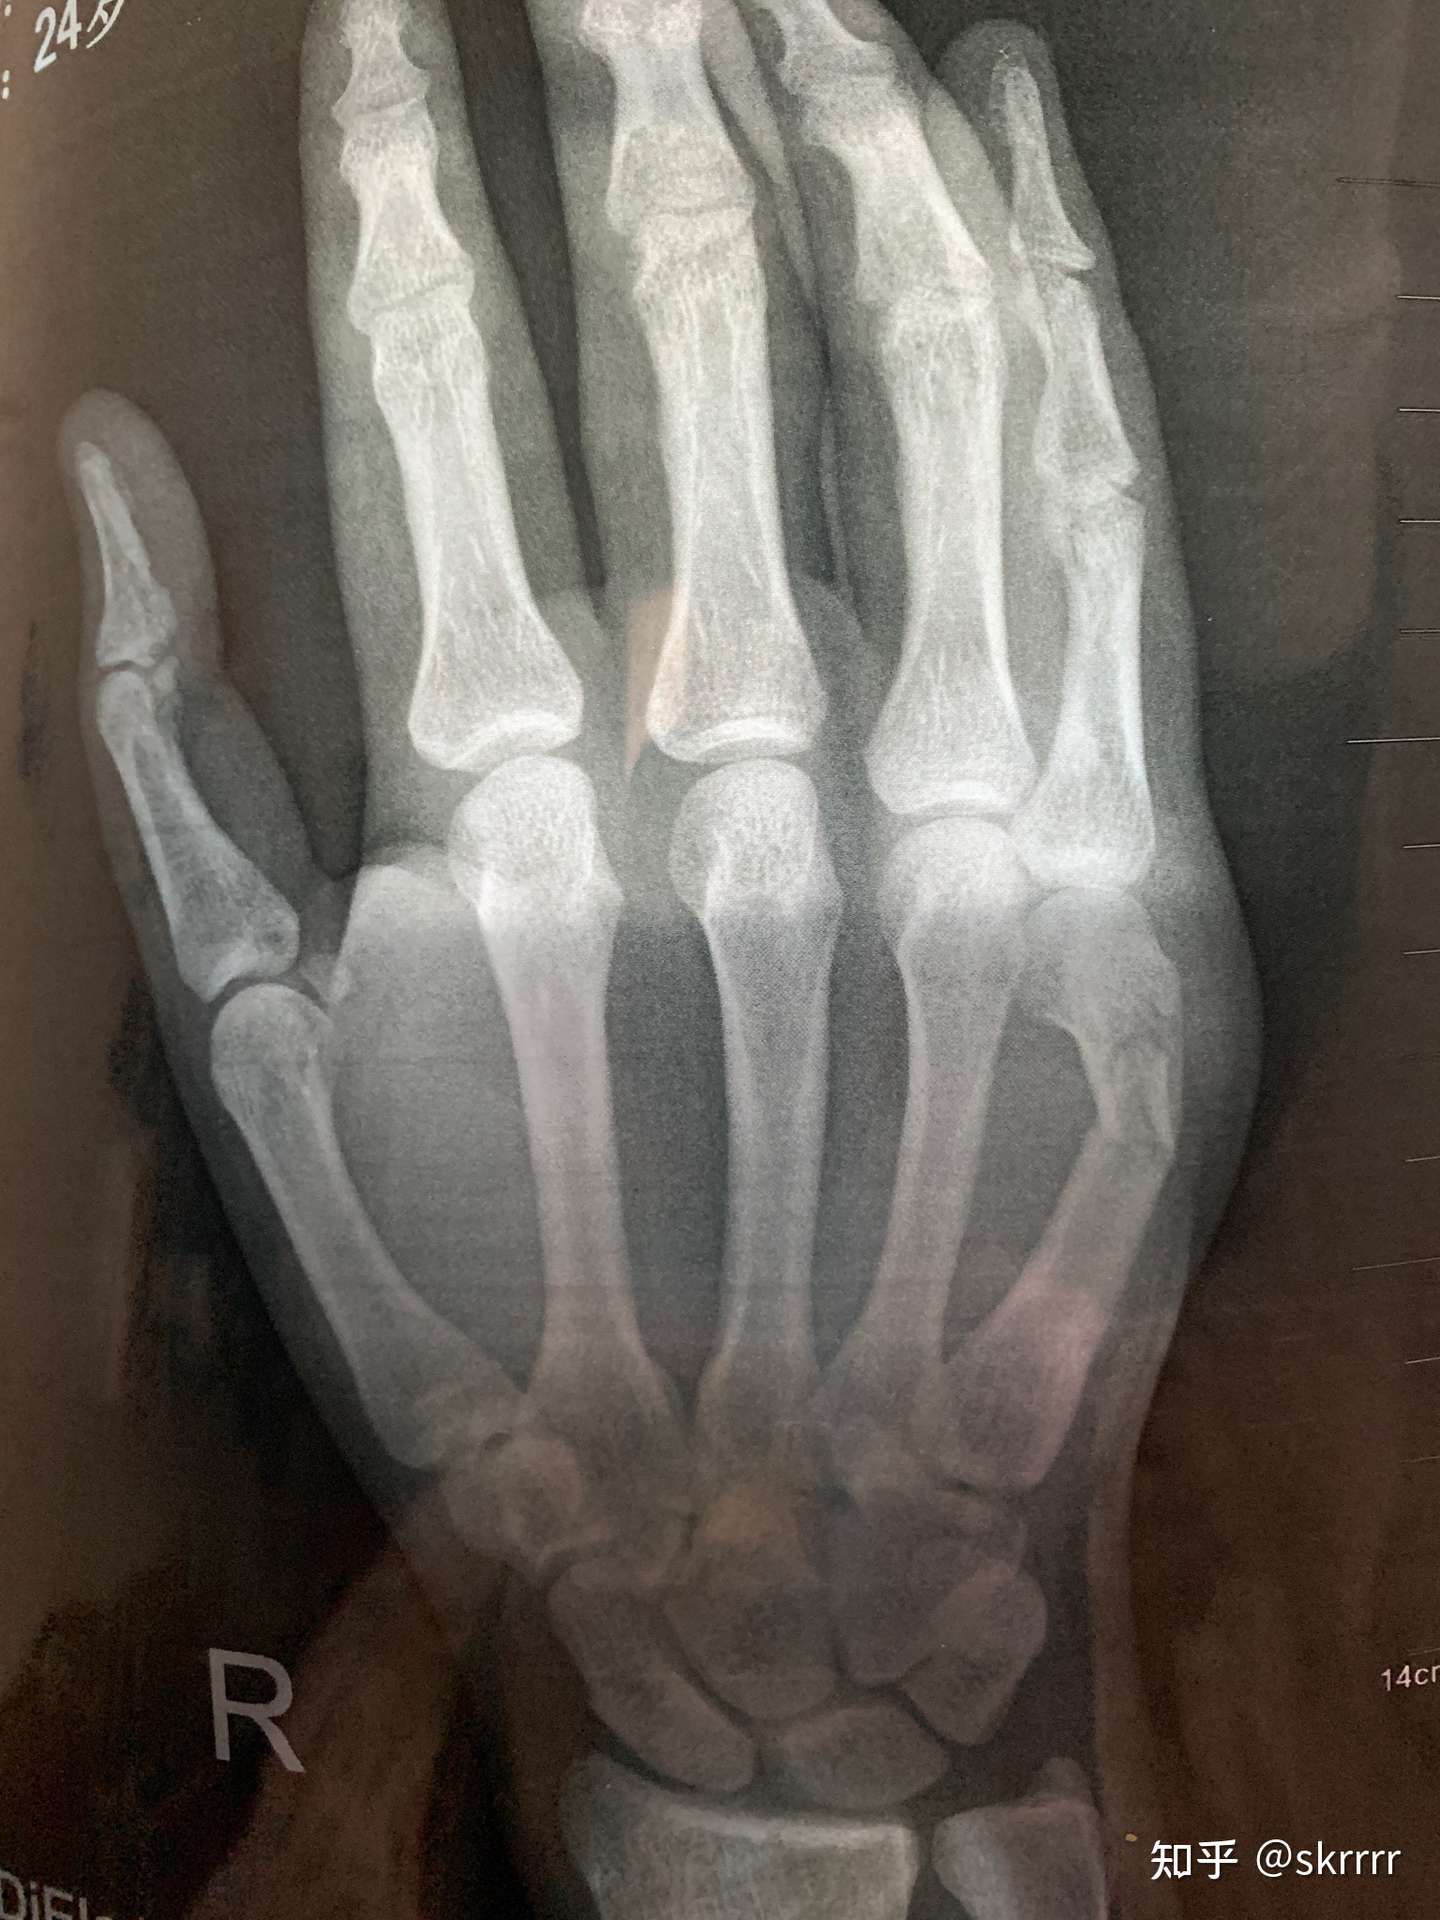

右手骨折 手術- 橈骨遠位端骨折は骨折の中でも、比較的多く見られる骨折です。 しかし、「橈骨遠位端骨折とうこつえんいたんこっせつ」と聞いてもピンとこない方がほとんどだと思います。 では、橈骨とはどこの骨で、どんな骨折なのでしょうか? 上の骨折部位 1.中手骨骨幹部 (こっかんぶ) 骨折 原因: 中手骨の中央部を骨幹部といい、この部での骨折です。 物が手の甲に当たるなど、強い力が直接骨に加わったり、手をひねる力が加わったりして発生します(図2、3)。 症状:

手首の骨折の治療法 手首の骨折の治療は、自然治癒力によって癒合させるのが基本です。 応急処置 応急処置は症状の悪化を防ぎます。骨折部がズレると治療行程が増えて、治療期間が長引きます。 まずは副木で手首の関節を固定します。 良いほうの右手の骨と比べて見ても、 ほぼ変わりないくらい骨折部分がきれいに治っていることがわかります。 この時点で、しっかり治ったことを確認して、 通院終了となりました。骨折部位によって骨の転位方向が変わります。 a, 基部:浅指屈筋腱付着部よりも 近位 で折れた場合は 屈曲変形(背側凸) が起こりやすく(図41) b, 中央:浅指屈筋腱付着部よりも 遠位 で折れた場合は 伸展変形(掌側凸) の変形になりやすい(図42) c, 遠位:受傷機転により変形方向が